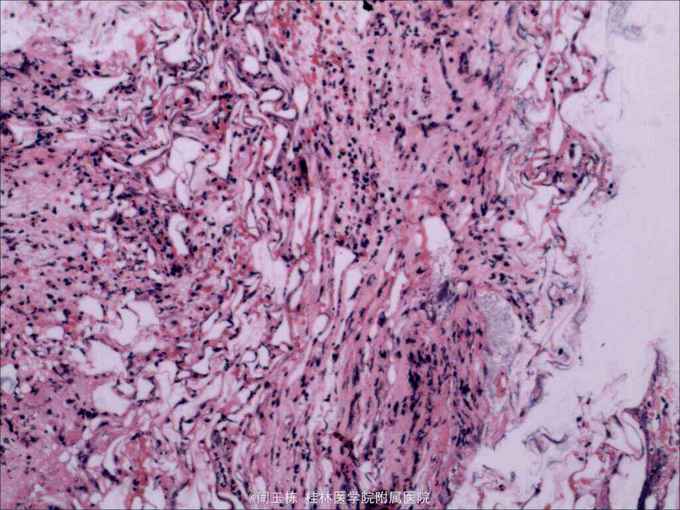

诊断十二指肠降段脂肪瘤,予内镜下切除。